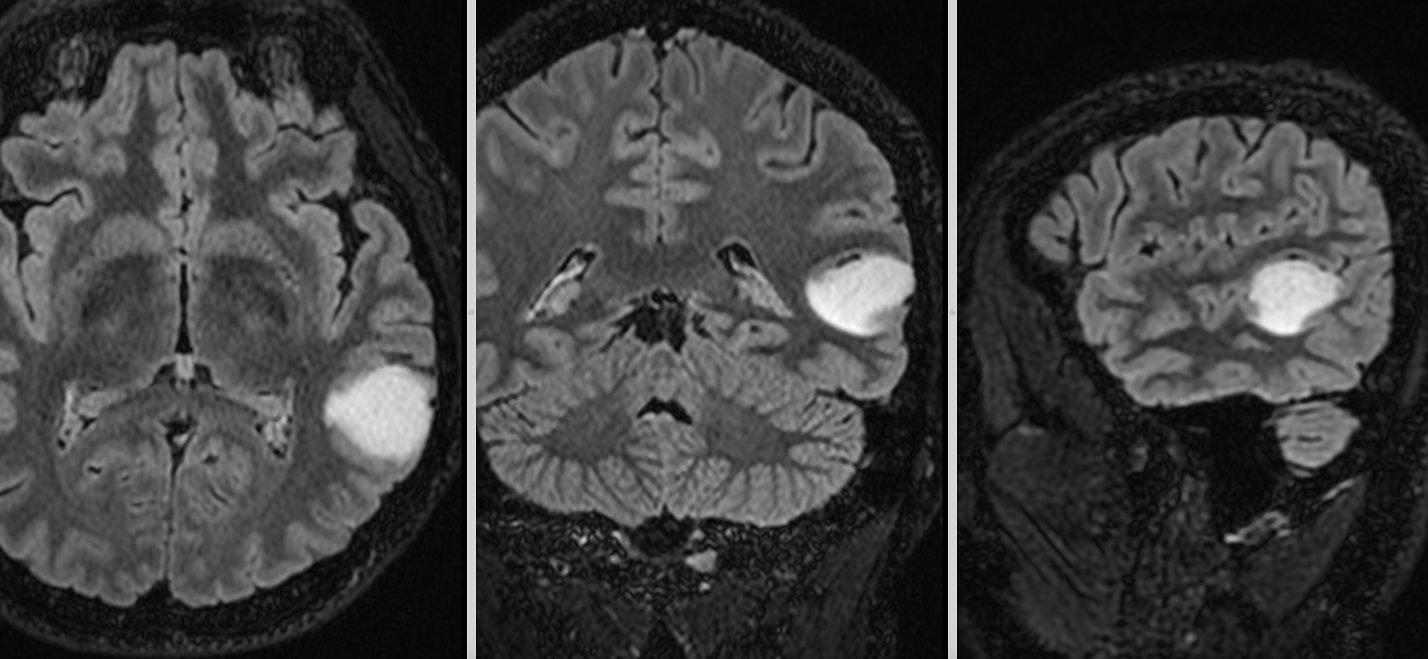

Vă prezentăm cazul unui pacient diagnosticat cu meningiom de aripă de sfenoid dreaptă, o tumoră cerebrală benignă care se dezvoltă...